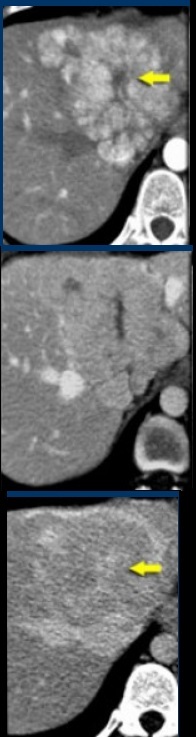

Diagnóstico = Hiperplasia Nodular Focal!

Na imagem, duas lesões hipervasculares adjacentes com realce homogêneo na fase arterial e cicatrizes centrais hipodensas na fase arterial e venosa, que aumentam na fase de equilíbrio. Isso é característico da HNF.

A HNF é considerada uma resposta hiperplásica e não neoplásica a uma malformação vascular congênita. Histologicamente, a HNF não é um tumor e consiste em hepatócitos de aparência benigna que ocorrem em um fígado que é normal (isto é, sem cirrose).

Na fase arterial tardia, a HNF tipicamente apresenta um realce homogêneo e brilhante, mas menos intenso que a aorta com uma cicatriz central hipodensa. (As faixas ou septos fibrosos hipodensos irradiados, oriundos da cicatriz, não são infrequentes e bastante característicos. Na fase portal, a HNF freqüentemente atenua o fígado normal e pode ser difícil de delinear.

A fase tardia freqüentemente mostra a hiperatenuação da cicatriz central e dos septos devido à opacificação tardia dos componentes fibróticos. Nenhuma calcificação, heterogeneidade ou cápsula deve ser observada na FNH.